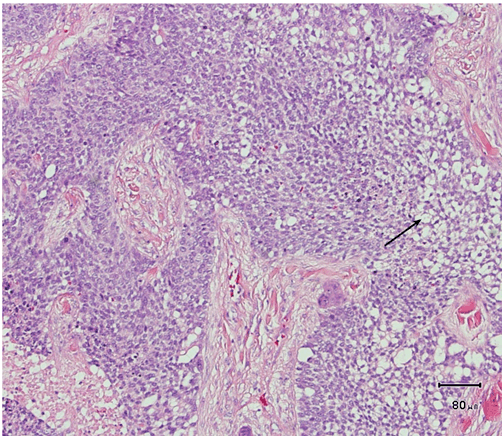

A 61-year-old male was presented to his dermatologist with a solitary nodular dermal lesion on his lower back (1.5x2 cm). He was otherwise well and was taking no medication. A biopsy demonstrated squamous cell carcinoma (SCC), and the patient was referred to our service for complete local excision. On follow-up, a month later, the patient presented with hemoptysis, hip-, and abdominal pain. Magnetic resonance imaging (MRI) scan confirmed the presence of lung, liver, and bone multiple metastases. As planned, a complete local excision with a 7.5 mm margin was performed. Histology confirmed the diagnosis of SCC. Furthermore, the patient had developed another solitary dermal lesion localized to the chin. This lesion was not present only a month prior during the visit to the dermatologist. A biopsy from this lesion also demonstrated SCC. The specimens from the back and chin were later studied with immunohistochemistry. The morphology suggested SC, with the tumor showing a solid arrangement of cells with nuclear pleomorphism, atypical mitosis, basophilic and vacuolated cytoplasm (Figure 1) and (Figure 2). In addition, immunohistochemistry showed tumor positive for epithelial marker Ber-EP4, pancytokeratin (Kl1) and epithelial membrane antigen (EMA) (Figure 3). Reactivity for p53 and proliferating cell nuclear antigen (Ki67) was high, showing 80–90% hot spots labeling of the tumor cells (Figure 4) and (Figure 5). Immunoreactivity levels of cancer protein p53 and Ki67 above 10 and 25% indicated a poor prognosis (Figure 6). It was then concluded that the correct diagnosis of both tumors was in fact SC and not SCC.

Figure 1: Solid arrangement of tumor cells with vacuolated cells to the right (arrow), (H&E stain, x100).